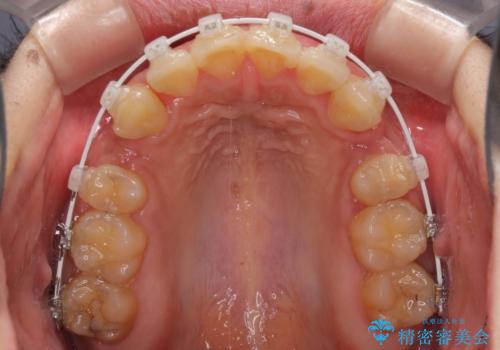

- 審美装置

- 口元の突出感と上下前歯のでこぼこを気にして来院された患者様です。

上下前歯部叢生のスペース獲得のため、上下顎左右小臼歯各1歯(計4本)を抜歯して、矯正治療を行うこととしました。

口腔内の清掃性に問題があり、虫歯のリスクが極めて高かったため、短期で治療を終えることを最優先に治療を進めました。